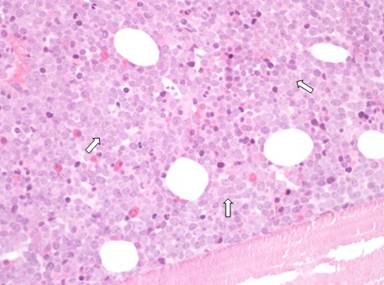

A 39-year-old man presented with a 4-month history of 6 kg weight loss and a 6-week history of upper abdominal pain radiating to the back with nausea and vomiting. He had no significant past medical history and apart from jaundice and tenderness in the upper abdomen, examination was normal. Laboratory investigations showed a haemoglobin concentration of 13.5 g/dL (reference range: 11.5-16.5 g/dL), total white cell count of 5.0x109/L (reference range: 4-11x109/L) with a normal differential white cell count, bilirubin of 6 µmol/L (reference range: 3-21 µmol/L) , alanine transaminase of 43 IU/L (reference range: 10-60 IU/L), and alkaline phosphatase of 175 IU/L (reference range: 25-125 IU/L). Computerised tomography (CT) showed a diffusely enlarged pancreas with dilatation of the common bile duct and intrahepatic biliary tree. The pancreatic mass measured 4 cm at the head of pancreas and 4.5 cm at the body. A single left para-aortic node of 1.7 cm was also found (Figure 1) but there were no other abnormalities. Radiologically, the differential diagnosis included autoimmune pancreatitis or primary pancreatic lymphoma, however, IgG4 levels, pancreatic autoantibodies and CA 19-9 measurements were unremarkable. Four weeks after the initial blood tests, bilirubin and alanine transaminase were stable but alkaline phosphatase had increased to 1,699 IU/L and the white cell count increased to 44x109/L. The blood film showed blast cells (33% of total white cell count) and subsequent bone marrow aspirate and trephine revealed a diagnosis of precursor B cell lymphoblastic leukaemia (Figure 2). Cytogenetics identified a t(4;11) chromosomal translocation with a mixed lineage leukaemia gene rearrangement.

Figure 2. Bone marrow trephine at presentation (x40). Cellular marrow with heavy infiltration by leukaemic blast cells indicated by the white arrows. |